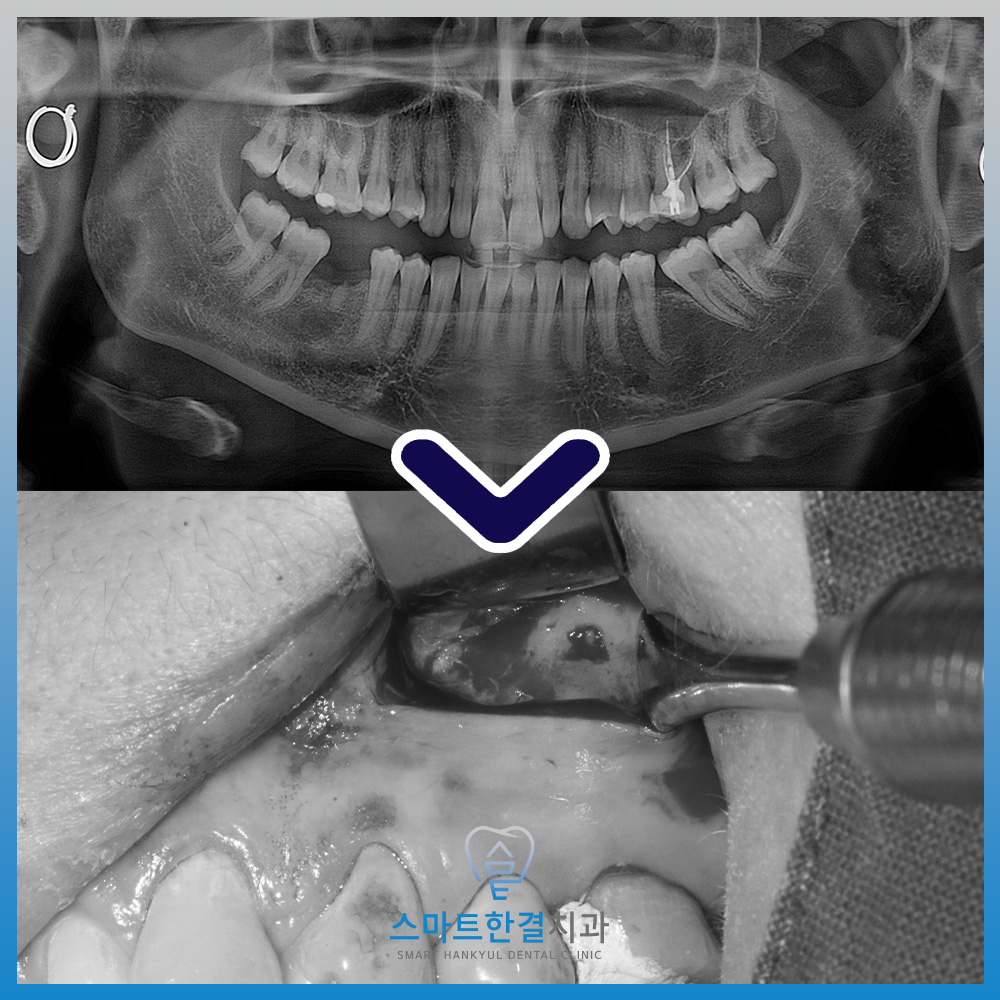

치아의 상태를 더 정밀하게 확인하기 위해

파노라마와 CT 촬영을 진행해본 결과,

치아 뿌리 끝에 염증이 있는

부분이 발견되었어요.

특히, 이 병소는 치아의 뿌리와

가까운 부위에 위치해 있으며,

상악동(코 위의 빈 공간)과

연결된 모습이 보였는데요.

즉, 치아와 상악동이

서로 영향을 주고받고 있는 상태로,

이로 인해 통증이나 불편함이

발생할 수 있답니다.

치료를 위해 잇몸을 열어보니,

치아의 뿌리 끝 부분에서

고름이 나오는 것을 확인할 수 있었어요

이 고름은 염증이 생긴 부위에서 나온 것이었고,

상악동(코와 연결된 부위)의 막과

잘 분리하여 염증이 있는 부분만

제거할 수 있었답니다.